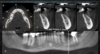

main difference between CBCT and MCDT (cat scan?)

A

CBCT = whole volume with single rotation

MDCT = one slide every rotation

How well did you know this?

1

Not at all

2

3

4

5

Perfectly

6

Q

components of CBCT

• xray generation

• xray detection

• image reconstruction

7

CBCT: continous or pulsed

pulsed preferred since it reduces patient radiation dose

8